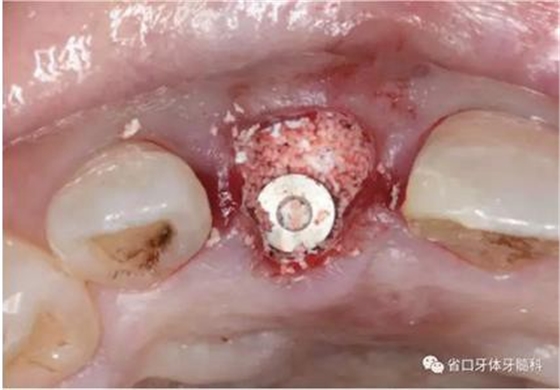

(1)微創(chuàng)拔牙及即刻種植:術(shù)前拍攝口內(nèi)照及實(shí)施牙周基礎(chǔ)治療。常 規(guī)消毒鋪巾阿替卡因局麻下微創(chuàng)拔除上頜右側(cè)中切牙,搔刮拔牙窩及根尖肉 芽組織。探測牙槽骨唇側(cè)骨壁及鄰面牙槽嵴完整,牙齦無撕裂。不翻瓣下于上頜右側(cè)中切牙缺隙近遠(yuǎn)中中點(diǎn)的腭側(cè)牙槽骨及根方定位,按照逐級預(yù)備的原則,緊貼牙槽窩腭側(cè)骨壁制備種植窩洞,植入Zimer®3.7mm×13mm TSV種植體1顆,植入扭矩>35N·cm,以O(shè)sstell測量種植體的ISQ值為68。 種植體平臺位于唇側(cè)齦緣中點(diǎn)下3mm,與唇側(cè)骨壁內(nèi)側(cè)面形成的跳躍間 隙約2mm,置入Bio-Oss®細(xì)顆粒骨粉0.25g,上愈合基臺關(guān)閉創(chuàng)口。術(shù)后 CBCT檢查顯示:種植體利用牙槽窩根方骨質(zhì)固位,緊貼牙槽窩腭側(cè)骨壁, 其唇側(cè)面與牙槽窩唇側(cè)骨壁的內(nèi)側(cè)面所形成的跳躍間隙(約2mm)可見顆 粒狀顯影物充填。牙槽窩的唇側(cè)骨壁及唇側(cè)倒凹無缺損穿孔。

圖16 跳躍間隙植骨

圖17 跳躍間隙植骨